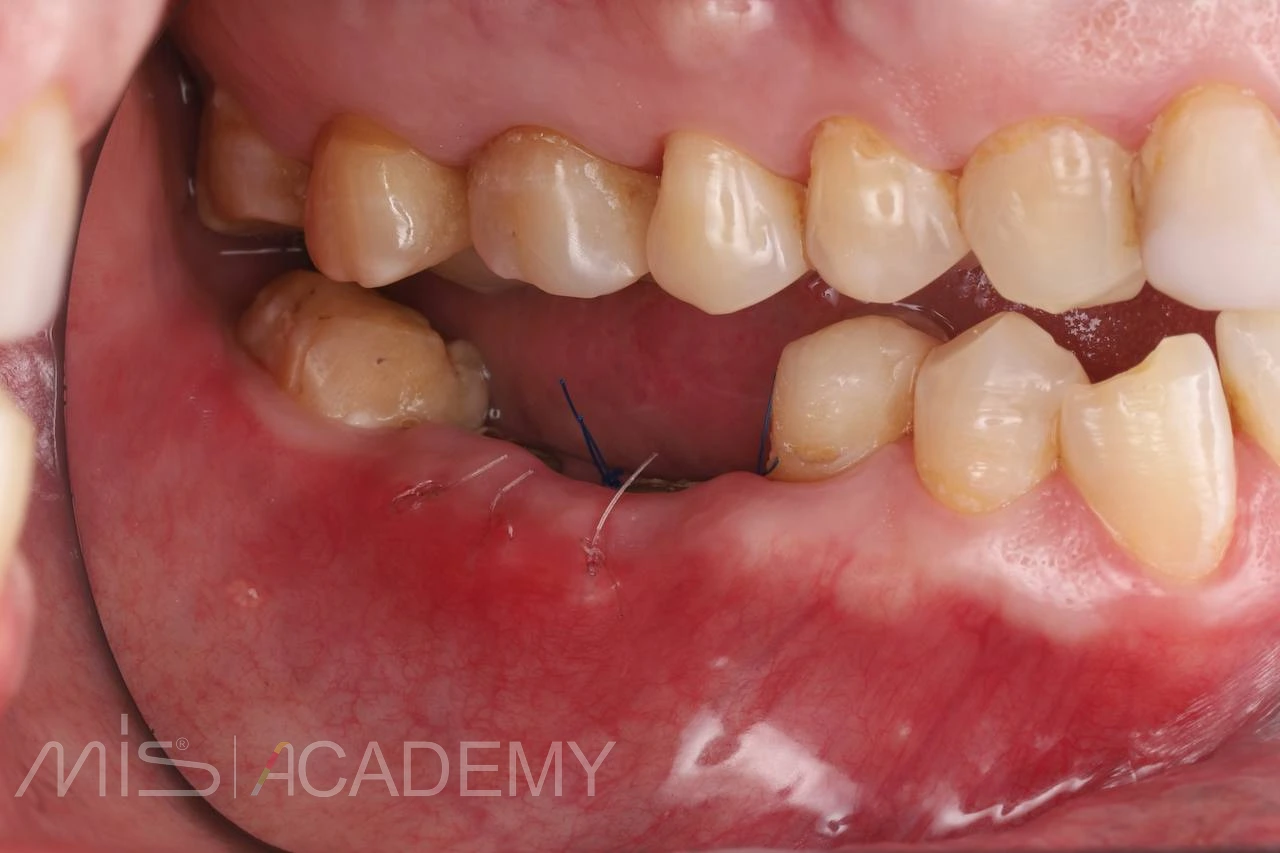

Устранение включенного дефекта зубного ряда на нижней челюсти, который в ходе лечения стал концевым.

— Имплантация 4.6, 4.7 MIS C1.

— Профилирование кости.

— Трансплантат с бугра под вестибулярный лоскут.

— Удаление зуба 4.8 после остеоинтеграции имплантов.

— Искусственные коронки из диоксида циркония на зуб 4.5 и импланты 4.6, 4.7 (2 месяца после фиксации).